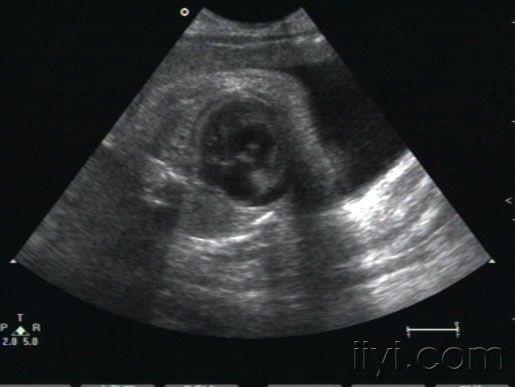

胎儿心包积液

• 孕38周,10天以前在多家医院检查胎儿正常。近一周来自觉腹胀,下坠。发现胎儿心包积液,并且右室壁好象很厚。胎儿生下来后,临床医生没有听到杂音,遗憾的是孩子也没来检查心脏。我们没有开展胎儿心脏,请各位专家帮忙看下,到底是什么原因,胎儿右室壁增厚考虑什么病,为什么生后没有杂音呢?